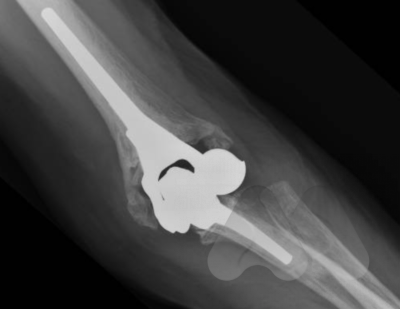

Total Elbow Replacement (TER)

TER has been used to treat patients with Rheumatoid arthritis in the past. As the medical management of Rheumatoid arthritis has improved over the last few decades, we have seen an overall reduction in patients requiring joint replacement. Patients with osteoarthritis or post-trauma now form an increasingly larger number of patients having TER, forming 70% of TER’s performed in Australia in 2019. The procedure involves removing the damaged joint surfaces and replacing the joint and inserting stems into the bone which are secured with cement. Overall 10 year survival in is 80-90%.

Specific risks of Total Elbow Replacement include, infection, fracture, nerve injury, loosening and dislocation.